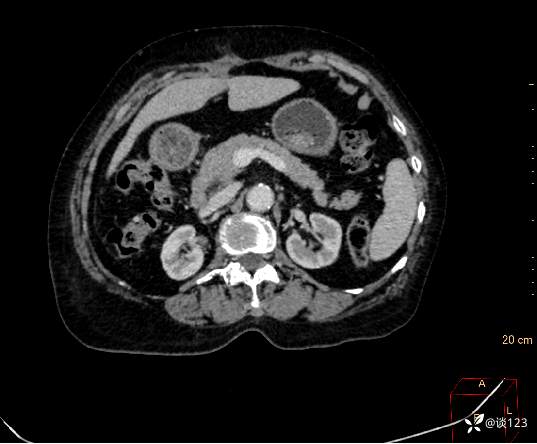

先做的CT:

C-

A

V

D

重新针对CT进行多参数后处理

这类病变不结合病史的情况,即使在CT静脉期有所异常也容易忽略;同时针对该类疾病使用胰腺增强方案应该更佳,好的诊断先决条件还是技术,技术不够CT新技术来凑。